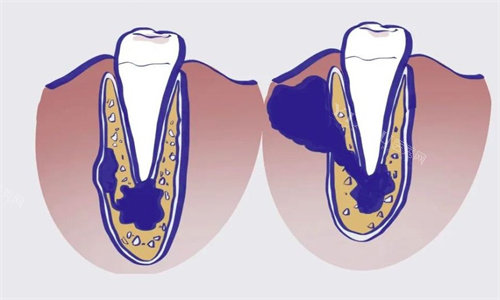

邻牙倾斜:缺失牙两侧的牙齿会逐渐向空隙倾斜,导致咬合紊乱;

牙槽骨吸收:拔牙后牙槽骨缺乏刺激,3个月内萎缩高度可达20%,影响后期种牙;

面部塌陷:前牙缺失若长期不修复,可能导致鼻唇沟加深、法令纹加重,加速面部衰老。

益众口腔理念:通过根管治疗清除感染牙髓,保留天然牙根,后续通过牙冠修复改善形态与功能,避免拔牙带来的连锁反应。

第三步:修复穿孔,重建牙根结构

MTA材料修补:若牙根穿孔直径≤1mm,使用矿物三氧化物凝聚体(MTA)修补,其生物相容性优异,可促进牙周膜再生;

引导组织再生术(GTR):穿孔直径>1mm时,联合使用胶原膜与骨粉,引导牙周组织再生,封闭穿孔部位;

实例:35岁的王先生因外伤导致门牙根尖1/3穿孔,直径约1.5mm。医生通过GTR技术修复,6个月后复查,穿孔处已形成新生牙骨质。